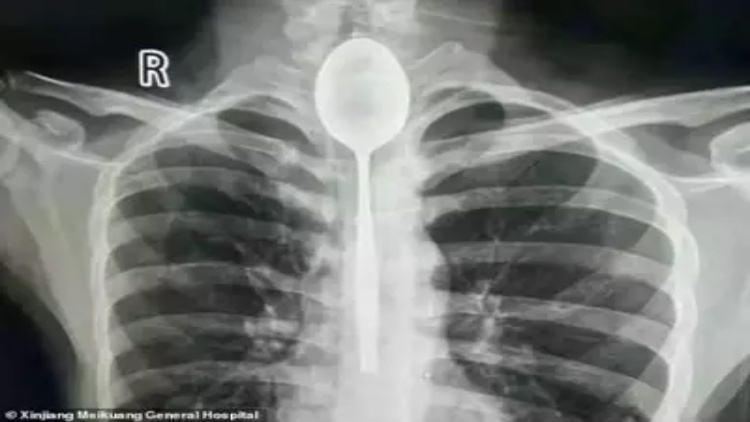

Dilansir Okezone dari OddityCentral, baru-baru ini seorang pria asal Xianjiang di Tiongkok melakukan suatu kecerobohan. Setahun yang lalu, ia menelan sebuah sendok dan tersangkut di kerongkongannya. Ia tak mengira kalau sendok itu tersangkut. Karena ia bisa makan dan minum dengan normal. Oleh karena itu ia tidak pernah meminta bantuan medis.

Namun, beberapa hari yang lalu ia mengalami nyeri di dadanya setelah dipukul pada bagian dadanya. Ia pun mengatakan pada sang dokter bahwa tahun lalu ia taruhan dengan temannya untuk menelan sendok stainless steel. Dalam keadaan sedang mabuk berat, dirinya menelan sendok yang diikat tali lalu menarik kembali sendok itu. Tapi, rencana itu ternyata tidak berjalan sesuai rencana.

Alih-alih langsung pergi ke rumah sakit, ia hanya menunggu dan melihat apakah akan mengalami kesulitan makan atau tidak. Saat mengetahui sendok itu tidak menimbulkan efek samping yang berarti, ia membiarkan sendok itu menempel di kerongkongannya selama setahun.

Sendok itu mungkin akan tetap berada di kerongkongan pria itu lebih lama jika ia tidak mendapatkan pukulan di dada. Pukulan itu menyebabkan ia kesakitan dan kesulitan bernapas. Dia akhirnya pergi ke Rumah Sakit Umum Xianjiang Meikuang untuk memeriksakan keadaannya.

“Saya terkejut. Saya tidak pernah mengalami hal yang seperti ini,” kata Dr. Yu Xiwu yang menangani pria ini, Minggu (28/10/2018). “Ketika kami memeriksa pasien, kerongkongannya sudah terinfeksi,” tambahnya.

Para petugas medis memutuskan untuk mengeluarkan benda tersebut dengan cara mengekstrak sendok melalui mulut. Pasien diberikan anastesi dan tim menghabiskan dua jam untuk mengeluarkan sendok berukuran 8 inchi menggunakan peralatan endoskopi. Pihak rumah sakit telah memberitahu kepada media bahwa pria itu sedang dalam tahap pemulihan dan akan segera dipulangkan.*** (okezone)